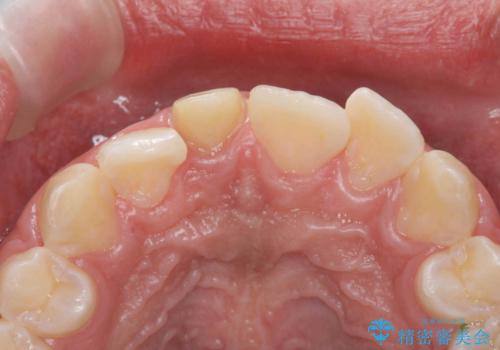

変色した前歯 根の治療とセラミックで白い歯に

- 前歯の変色を主訴に来院。

神経が死んでいたため、神経の治療を行いました。

また、全体的に歯石がついており、歯ぐきから出血しやすい状態であったため、TBI(歯磨き練習)を行い、歯茎の炎症をしっかり収めてから治療しました。

今後矯正治療をするかもしれない(未定)とのことでした。

その際、支障がでないように、患者様と相談し、他の歯を削って並びを整えるようなことはせず、前歯の角度はそれなりにそろえる形にしました。

神経が死んでしまった歯は時間がたつと変色してきてしまいます、セラミックでかぶせると色を改善することが可能です。